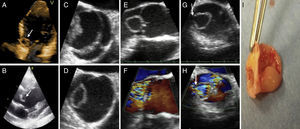

A 28-year-old man with no relevant medical history was admitted to our hospital for fever occurring early in the evening, weakness, dyspnea, and headache of 2 months’ duration. Blood culture was persistently positive for Streptococcus sanguinis (5/5). Upon admission, a diastolic murmur that had not been detected previously was found. Transthoracic echocardiography was performed and showed a large aneurysm in the noncoronary leaflet of a bicuspid aortic valve, severe aortic insufficiency, and left ventricular dilation (Figures A and B). Transesophageal echocardiography identified perforation of the aneurysm as the cause of aortic insufficiency (Figures C-H). After the patient had completed antibiotic treatment and blood cultures tested negative, a decision was made to operate due to persistent dyspnea in the presence of severe aortic insufficiency. The same findings were observed (Figure I) as described above.

Aortic valve aneurysms are rare, with fewer than 15 cases reported in the literature. Although the most probable cause is infectious endocarditis, this disease has been demonstrated in only a few cases. Our case met 2 of the major Duke criteria and 2 minor criteria for the diagnosis of definite infectious endocarditis: positive blood culture, new valvular insufficiency, fever, and predisposing heart disease. Ultimately, the valve culture was sterile, but surgery was done after completing antibiotic treatment and achieving negative blood cultures.

As in other published cases, there was an absence of characteristic images of endocarditis accompanying the aneurysm. Therefore, an isolated finding of aortic aneurysm advises assessing for infectious endocarditis to rule out the presence of this condition.